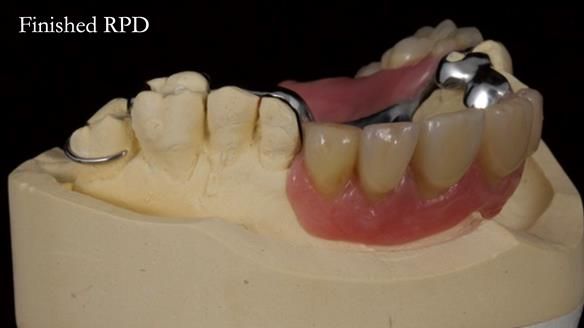

Keith’s combat denture case study

Keith’s case was one of the most challenging and rewarding cases I’ve treated this year. This 64 year old man presented with ill-fitting acrylic partial dentures that lacked stability, retention, and aesthetics. They constantly broke. He had lost the upper front teeth in a road traffic accident in his early 20s. The unopposed teeth had erupted, taking up space. After careful planning, we made a durable, metal-based upper partial denture/splint to address his dental concerns. He loved the outcome.

1. Denture design: A custom cobalt-chromium framework was Scandinavian-designed to maximise stability, protect the remaining teeth, and allow for future additions if needed.

Keith’s denture incorporated a Duracetal shell clasp on upper right first premolar (Myerson), which are designed to be virtually visible, providing a more aesthetic solution while enhancing patient comfort. The Scandinavian-inspired approach, based in modern removable prosthodontic techniques, ensured the denture was not only durable but also visually pleasing. Additionally, the design was carefully planned to allow for future modifications, ensuring that if Keith loses additional teeth, the denture can be adapted rather than replaced entirely.